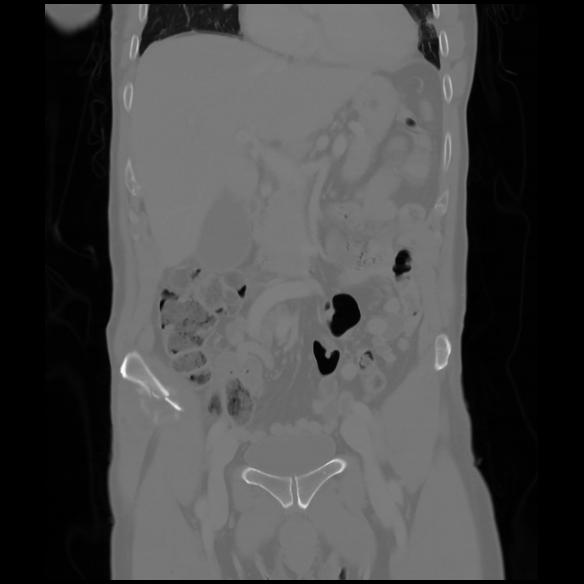

6 CUERPO,CE,Coronal,3.000,CUERPO,Coronal,